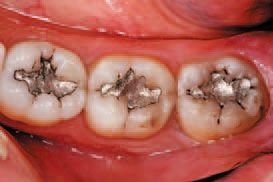

A healthy 45-year-old male patient presented with occlusal amalgam fillings that were placed more than 20 years previously. A treatment plan was agreed upon involving the restoration of tooth Nos. 30 and 32 using a Tetric EvoCeram® Bulk Fill composite, and tooth No. 31 using both a flowable and universal composite (Tetric EvoFlow® and Tetric EvoCeram®).

After inspecting the old amalgam restorations (Fig. 2), a rubber dam was then placed (Fig. 3). Next, using Sybron Dental’s Axis course diamond bur, KS3, the amalgam restorations and all damaged tooth structure were removed (Fig. 4).